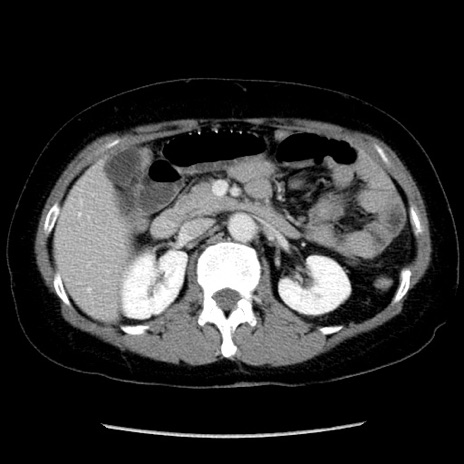

症例6(横断像)

【症例】50歳代女性

【主訴】下腹部痛

【現病歴】本日朝より下痢2回あり。 昼食を食べた後、嘔吐3回、下腹部痛認め、症状軽快せず、当院救急搬送。

最終食事:本日昼(生ものなし)。 昨日の夜、刺身を食ぺたとのこと。周囲に同様の症状の者なし。普段、排便は毎日あるとのこと。

【既往歴】卵巣癌術後(8年前に当院で卵巣摘出)

【身体所見】 意識清明、腹部:平坦、腸蠕動音→、やや硬、下腹部自発痛・圧痛あり、反跳痛あり、筋性防御なし。

【データ】WBC 16000、CRP 0.01